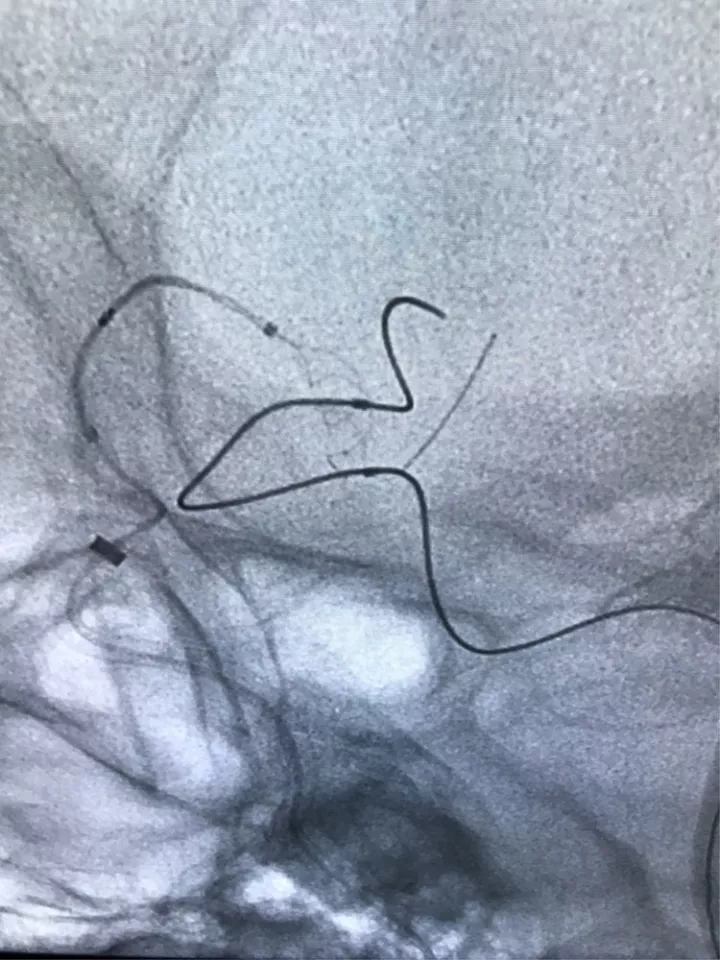

塑型后的形状

利用微导管的形状,将微导丝送入后交通动脉

微导丝走远

支架微导管到位

填了一个HydroFram8×30的弹簧圈成篮,从形态来看,应用双微导管技术栓塞是能够完成手术的

Enterprise4.5×22支架半释放,支架尾端的有效段能恰好覆盖全瘤颈

支架有效段完全释放,这个时候开始将支架导管往前顶,让导管头端尽量越过瘤颈远端

支架完全释放